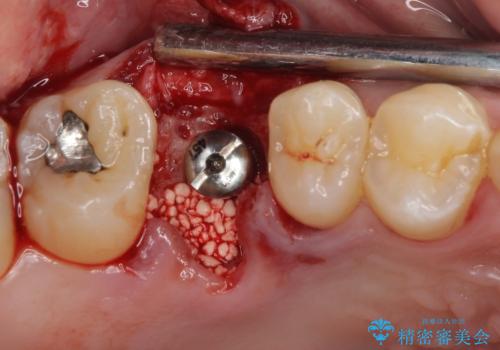

インプラント処置は、抜歯即時埋入を行い、十分な安定性が確認できたため、当日仮歯を装着しました。